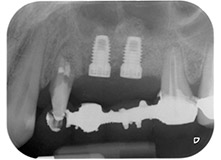

Накрая, след периостален разрез, мястото е пасивно зашито с коронарно напреднало ламбо, използвайки 5-0 абсорбиращ конец (Фиг. 15). Следоперативната рентгенова снимка показва, че и двата импланта са в правилна вертикална позиция (Фиг. 16).

Следоперативна рентгенова снимка

Фиг. 16: Следоперативната рентгенова снимка показва, че имплантите са на място и костозаместващия материал от вътрешния синус лифт около апекса. Има малко видим материал от GTR процедурата около каналите на зъб 24.